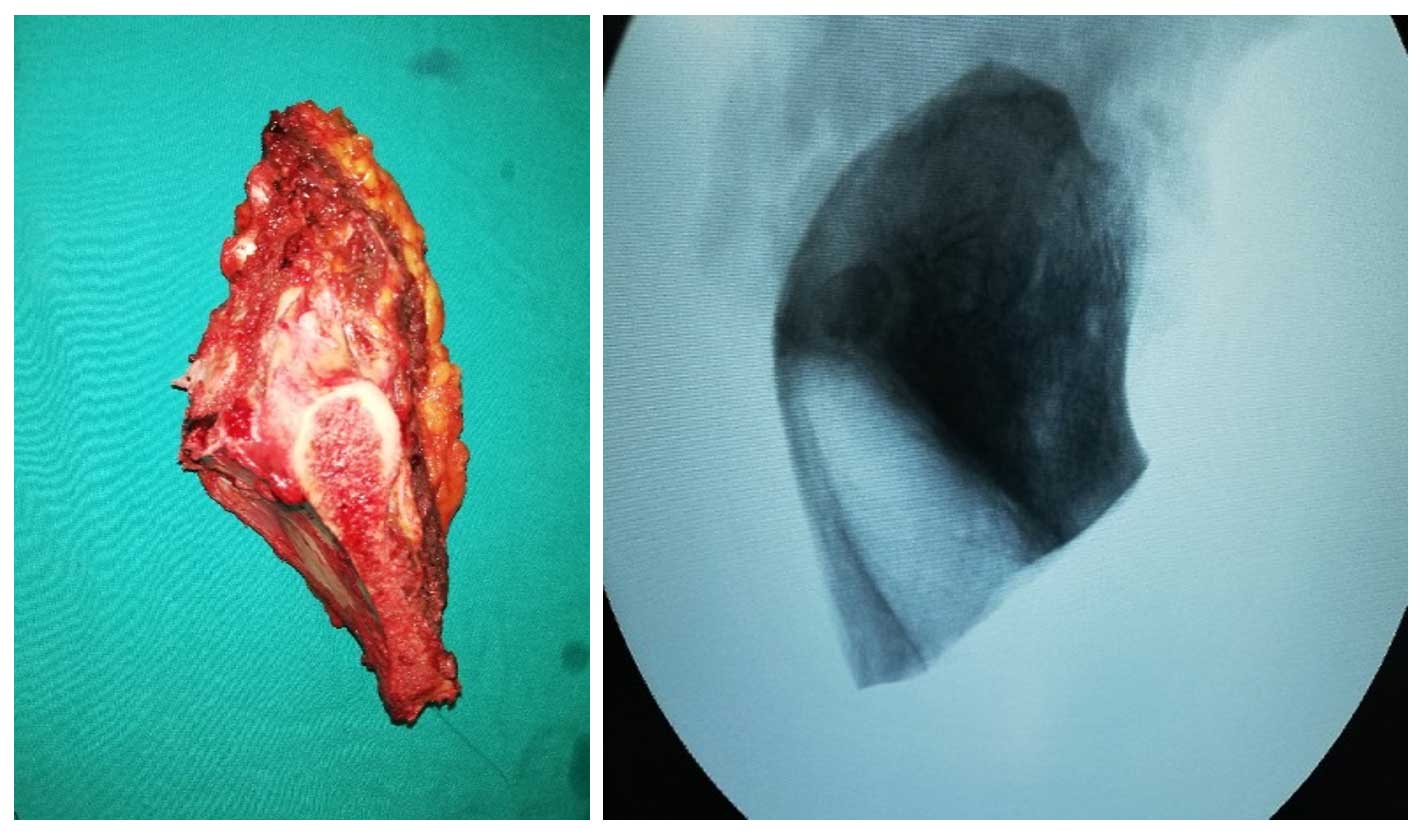

Ameliyat Esnası: Çıkarılan rezeksiyon dokusunun klinik ve radyolojik görüntüsü.